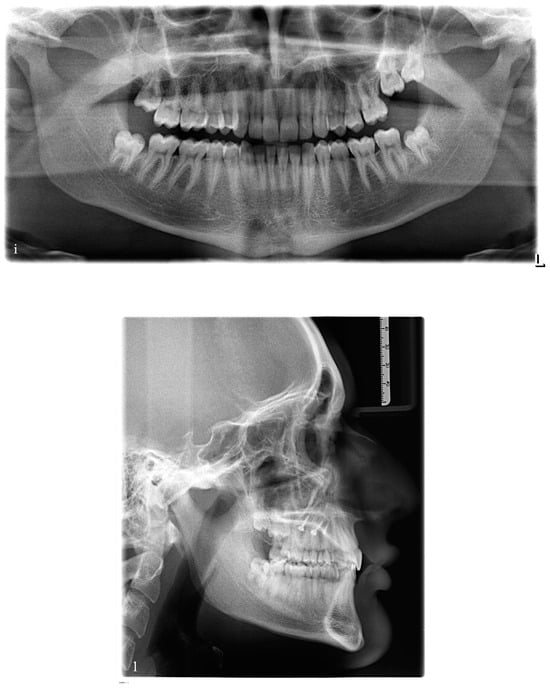

2.3. Case Description

2.4. Treatment Objectives and Alternatives

- The first option, corresponding to our choice, involved the distalization of the upper right quadrant in order to reach the molar and canine Class I occlusion and to correct the upper midline deviation. At the same time, it involved the mesialization of the upper left quadrant in order to close the spaces opened during the treatment.

- The second option involved the extraction of the upper right first premolar in order to correct the Class II canine relationship and the deviation of the upper midline.